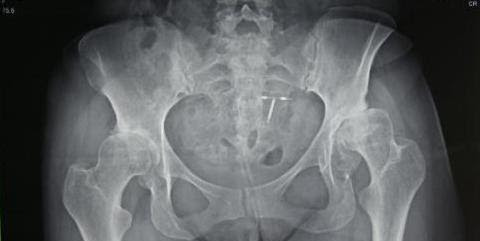

Marciela's x-ray prior to her 2018 surgery

Marciela Arevalo was one of our patients during the 2018 CAMTA mission, where she received a bilateral hip replacement. Her one year follow up with Dr. Tim Kostamo went so well she came out of his office dancing in her high heels! She expressed her thanks to the team and plans to keep dancing! We love these success stories!